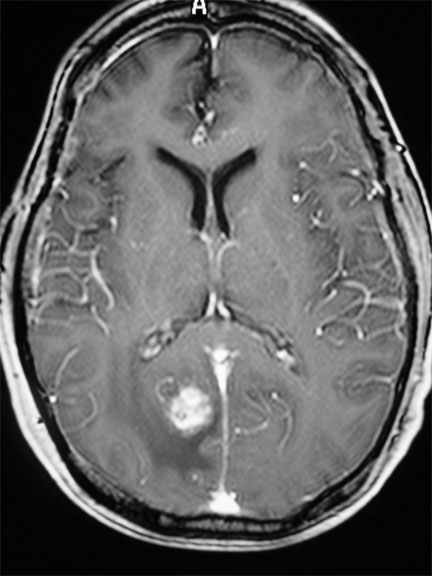

Control a 3 años post radiocirugía: En lugar del tumor se observa una mínima cicatriz. Los síntomas desaparecieron y el paciente retomó su vida profesional habitual